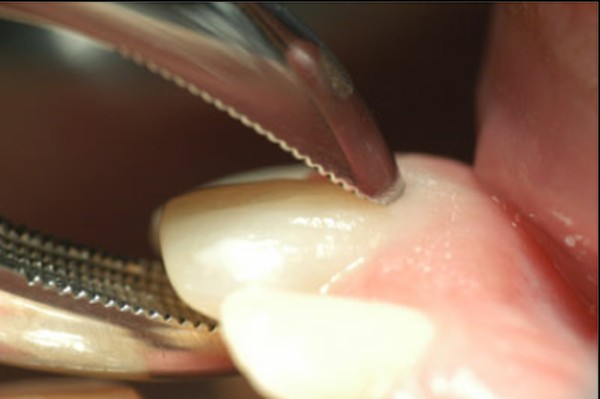

Las extracciones dentarias o EXODONCIAS, son habitualmente realizadas mediante la utilización de instrumentos denominados FÓRCEPS, los que instalados en el cuello de la pieza dentaria a extraer, son movidos de manera oscilante en el eje del diente, lográndose después de un corto período de tiempo, quitar al mismo de la cavidad ósea que lo aloja, en una operación que se denomina LUXACIÓN o AVULSIÓN. FÓRCEPS EN BOCA Esta AVULSIÓN, se produce debido a que el hueso es elástico. Sin embargo , gran parte de las veces esa elasticidad no es suficiente y se parte o rompe la «corteza ósea» que rodea al diente, en su región más cercana a la «zona cortante» del mismo.Esa ruptura o fractura, es favorecida por el uso de los Fórceps, dado que sus «mordientes» se sitúan muy cerca de del hueso. .FÓRCEPS ROMPIENDO LA TABLA TABLA ROTA La idea de crear un instrumento que impida dicha fractura, se basa en la certeza de que cuanto más adentro del diente, y cuanto más cerca de la punta del diente, se efectúe la fuerza de AVULSIÓN, menos posibilidades de fractura existirán por una simple cuestión de física básica: CUANTO MÁS LARGO SEA EL BRAZO DE POTENCIA DE UNA PALANCA, MENOS ACCIÓN TENDRA EL BRAZO DE RESISTENCIA….POR LO TANTO SERÁ NECESARIA MENOS POTENCIA PARA VENCER LA RESISTENCIA… O SEA, CON MOVIMIENTOS MAS DELICADOS , LOGRAREMOS EL MISMO EFECTO. ESQUEMA DE DIENTE MOSTRANDO LA ACCIÓN DE LAS FUERZAS DE UN FÓRCEPS. ESQUEMA DE DIENTE MOSTRANDO LA ACCIÓN DE FUERZAS DE UN AIDA Cuando la especialidad IMPLANTOLOGÍA, no se había desarrollado tal como ahora la conocemos, la fractura de esa «corteza ósea» denominada TABLA EXTERNA O INTERNA del PROCESO ALVEOLAR, carecía de importancia ya que la cicatrización se produce irremediablemente en ausencia de infecciones Sin embargo, a la luz de los conocimientos actuales, la preservación de dichas TABLAS, son de capital importancia para la realización de un IMPLANTE INMEDIATO(Implante colocado en el mismo acto quirúrgico que la extracción), y para el logro de su INTEGRACIÓN Y ESTÉTICA futura. Es por eso que exponemos ante las autoridades competentes, la idea de patentar un instrumento como el que denomino: AVULSIONADOR INTRADENTARIO ATRAUMÁTICO …cuyas características principales son: MATERIAL: ACERO QUIRÚRGICO 316 LONGITUD TOTAL:13 mm PUNTA ACTIVA: 6 mm FORMA DE PUNTA ACTIVA: HELICOIDAL DECRECIENTE DOS GROSORES DE PUNTA. INSTRUMENTO AD HOC Por acción de las espiras , el instrumento se fija en las paredes del canal dentario, produciendo un anclaje que permite la AVULSIÓN. CRESTA ÓSEA COMPLETAMENTE CONSERVADA